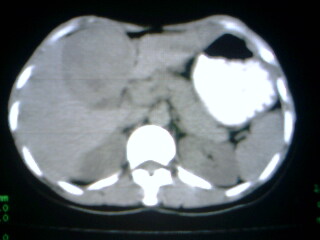

标题: CT9794:女 35Y 近两个月腹痛纳差明显消瘦 [打印本页]

标题: CT9794:女 35Y 近两个月腹痛纳差明显消瘦

在上几个层面肝脏有被病灶撑开的征像,病灶应该还是在肝上的,那就要考虑个猛的了,患然挺年轻,但对不住了,考虑肝癌

病人应该没有肝硬化病史,考虑胆囊癌可能性大,建议增强扫描除外肝腺瘤\\fnh等良性病变.

病变来自胆囊可能性大

增强,查afp。病灶象在肝内,若在胆囊内,肝内外胆管应有明显改变。

右肝癌。

巨大肿块。